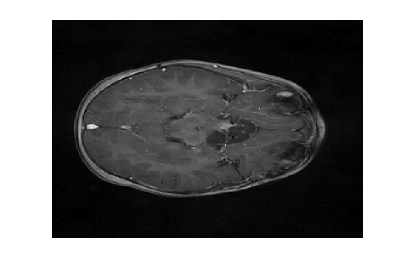

Figure 2: Image reconstruction from Case 20 (a, b, and c) and Case 3 (e, f, and g) of a brain image. Case 20 is the best performing algorithm that uses L1-W and case 3 is the best performing algorithm that uses LACS-MRI

The phantom image that we used in the previous experiment is flat and has less texture while the brain images has a lot of wrinkles and complex shapes. While the phantom image is small, the brain image is too large to calculate fNDsubscript𝑓𝑁𝐷f_{ND} efficiently. Thus, we conducted an experiment in the same setting as the phantom image excluding cases using fAsubscript𝑓𝐴f_{A}: cases 6 through 8 and 14 through 16. In this experiment, contrary to results for the phantom image experiment, L1-W performs better than LACS-MRI. For example, Case 3 performed the best among cases using LACS-MRI but it performs worse than 6 cases that use L1-W. Interestingly, one of the cases that shows an outstanding image recovery purely uses fVDSsubscript𝑓𝑉𝐷𝑆f_{VDS} with L1-W. However, purely using fVDsubscript𝑓𝑉𝐷f_{VD} with L1-W shows a dramatically worse performance. In conclusion, we are unsure why each combination of mixed PDFs and reconstruction algorithm perform differently based on the images processed, but this differing behavior is crucial to highlight for practical applications. We conjecture that the texture of the image is one factor that decides the performance of each algorithm. In the future, we may explore this conjecture and analyze why this happens.